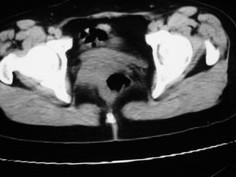

女42岁肛门下坠感4月余.

子宫轻度右倾,体后方见小似新月形低密度区,边界清楚。余所见无明显异常。

考虑:子宫直肠窝少量积液(盆腔炎所致)。

子宫轻度右倾,体后方见小似新月形低密度区,道格拉斯窝周围间隙欠清晰,有索条模糊影阴,多考虑:肛周脓肿可能性大。

肛周脓肿临床症状比较典型,此患者:女42岁肛门下坠感4月余,与其不符

子宫轻度右倾,体后方见小似新月形低密度区,道格拉斯窝周围间隙欠清晰,有索条模糊影阴,多考虑:肛周慢性感染可能。